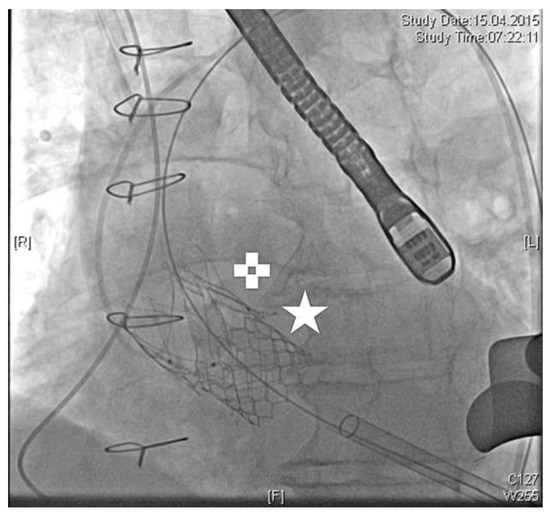

We present a case of false deployment of a self-expandable transcatheter aortic valve implantation (TAVI) prosthesis due to inadvertent and incorrect release of an eyelet in the crown of the valve resulting in a tilted valve. Hence the prosthesis had...